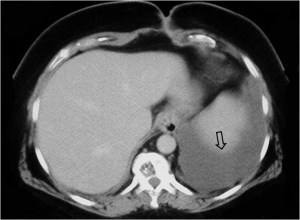

Este signo nos permite diferenciar entre derrame pleural y ascitis en un estudio de TC. Cuando existe una interfase nítida entre líquido y el hígado o el bazo, se trata de ascitis; cuando la interfase no es nítida, se trata de derrame pleural (flecha). El derrame pleural ocupa una posición más posterior y medial, mientras que la ascitis se localiza anterior y lateral al hígado y al bazo.